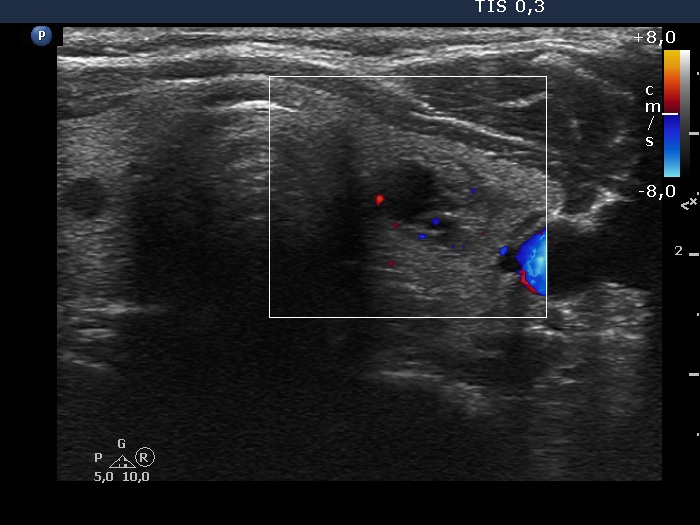

Left lobe, transverse scan, color Doppler mode. The vascularization is scanty.